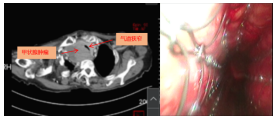

患者为83岁老年女性,甲状腺结节性肿大病史10年,未予治疗。半月前,其胸闷、憋气等症状呈进行性加重,并伴有喘息。胸部增强CT检查提示甲状腺右侧叶体积增大,伴异常强化肿块,周围血管、气管及咽喉部呈受压改变。患者胸闷憋气症状持续加重,严重时出现呼吸急促、不能平卧,伴喘鸣及大汗,后经多方咨询就诊于清华大学附属垂杨柳医院胸外科。胸外科立即联合麻醉科、ICU组织多学科术前讨论,于2025年6月24日为患者实施电子气管镜下气管支架置入术。手术过程顺利,支架置入后患者喘憋症状即刻获得显著改善。

术前CT 术中支架置入